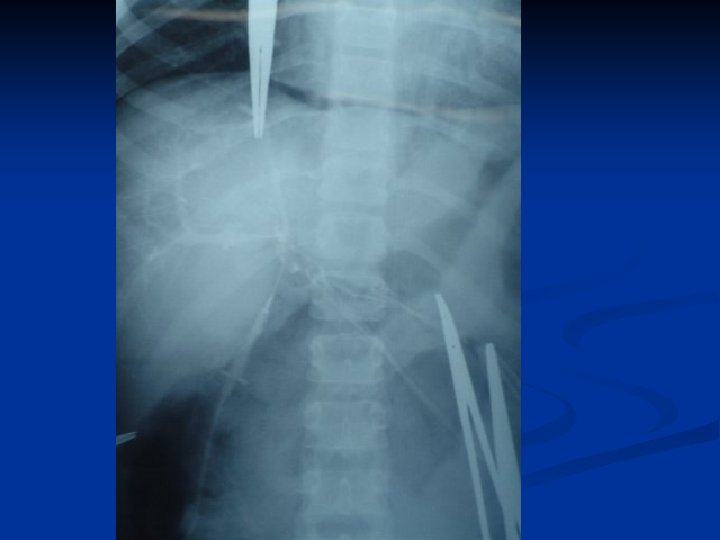

CONCEITO DO REX SHUNT MESO-LEFT PORTAL BY PASS 1 - LOCALIZAÇÃO PELO LIGAMENTO REDONDO DO FÍGADO DO RAMO ESQUERDO DA VEIA PORTA- INTRA HEPÁTICA 2 - DETERMINAR PATENCIA DO FLUXO PORTAL INTRAHEPÁTICO 3 - REALIZAR SHUNT MESENTÉRICO –PORTA ESQUERDA – JUGULAR- ILÍACA

Casuística pessoal – 12 casos n n Menino 9 anos – TVP Inúmeras internações por sangramento digestivo- 23 escleroterapias de varizes. Esplenectomia aos 3 anos Rex Shunt com jugular interna n Follow up- 5 anos - Sem complicações sem varizes esofágicas Otimo desempenho escolar n

Casuística pessoal – 12 casos n Menina 7 anos -TVP- inúmeras internações por sangramento digestivo- 32 escleroterapia de varizes. n Rex Shunt com jugular interna Trombose de Shunt com 6 mêses Novo Rex, com Ilíaca Interna Follow up- 4 anos Sem sangramento – Baço sp. Sem Varizes esofágicas Otima aprendizagem escolar. n n n